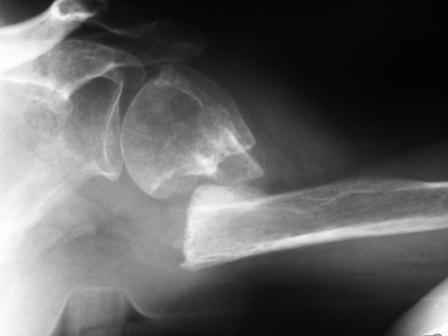

Уважаемые коллеги! Госпитализирована больная 51года. Травма - перелом хирургической шейки плеча в феврале 2009г.

Лечилась по месту жительства Лонгетной гипсовой повязкой. На фоне сформировавшегося ложного сустава работает маляром. Объем движений и сила естественно ограничены. При обсуждении тактики лечения возникли разногласия по поводу вида остеосинтеза и егоцелесообразности.